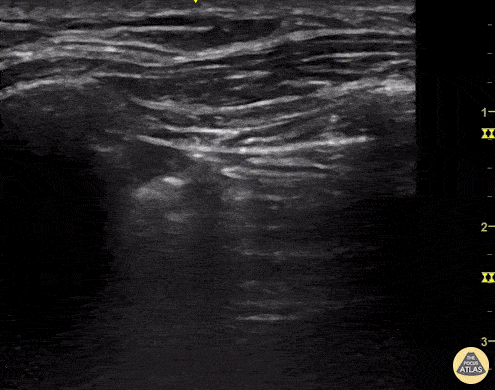

Pulmonary - Lung Point

A young man presents to the emergency department with multiple thoracic stab woulds. POCUS quickly identifies absent lung sliding as well as a lung point; findings highly sensitive and specific for our diagnosis of pneumothorax. Renato Tambelli, @R_Tambelli Emergency Physician Hospital das Clínicas de Marília